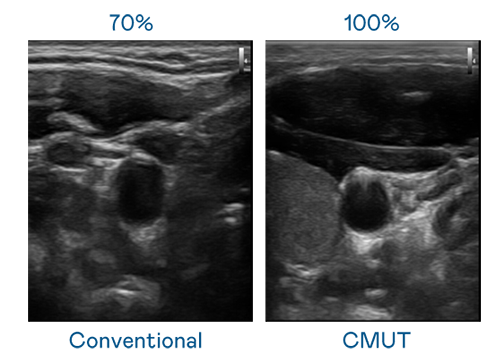

CMUT 技术是一种用电容式微机电元件来产生超音波讯号的技术。与传统 PZT 压电式技术相比,CMUT 频宽增加 30%,更宽频的超音波讯号让影像解析度大幅提升,是实现高影像品质医疗超音波扫描、促进精准医疗发展的关键技术。

超音波影像的解析度高低,首先取决于探头能发出的讯号频宽。918博天堂 CMUT 可提供高清晰的超音波讯号,提供高频宽、高灵敏度、影像纹理细节更高的超音波影像,协助医护人员缩短影像判读时间及利用精准的医疗影像进行诊断。